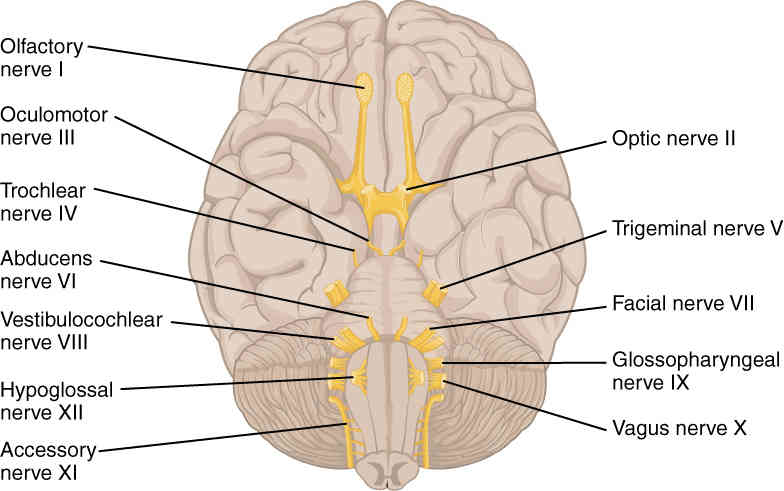

This page is under construction. For now, it is just a resource of the images found in the OpenStax Anatomy and Physiology Handbook. It wil slowly change into a revision tool. Each slide has a number. Use this to refer to the slide. When completed, it will have an unlabelled section, with labelled slides in parallel. On the unlabelled slides, write your answer and use the labelled slide to assess yourself. Keep track by also noting the number on each slide. Improvement at each attempt is important, more so than full marks on a first attempt.